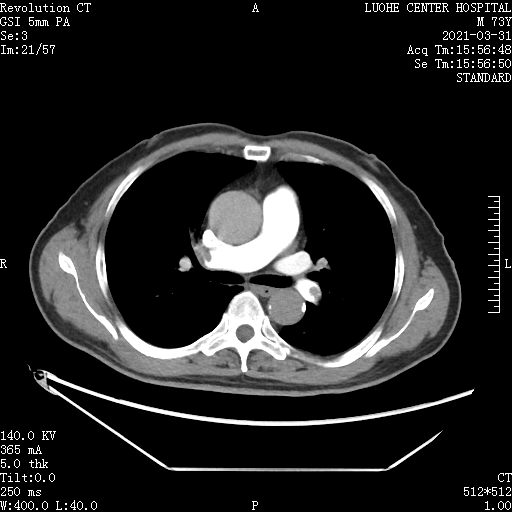

完善肺动脉CTA提示: